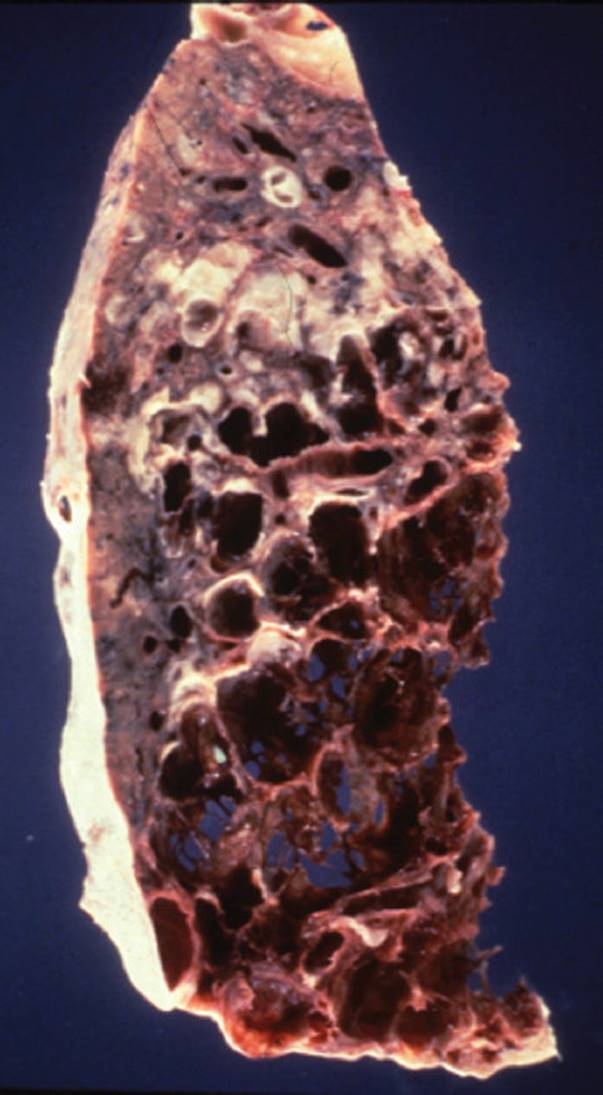

Emphysema is the second most prevalent disease within the category of COPD, with only asthma having a higher incidence. Emphysema is characterized by abnormal, irreversible enlargement of the airways distal to the terminal bronchioles, leading to decrease in driving pressure and intraluminal pressure, which leads to the impairment in expiratory airflow and maintenance of airway patency during inspiration28,29 (see Figs. 7-4 and 7-5). This may result in destruction of the acini, which are the functional units of the lungs for gas exchange. Each acinus is composed of one to three respiratory bronchioles and the alveolar ducts and sacs.

FIGURE 7-5 Emphysema. This disease results in the destruction of bronchioles and parenchymal tissue, which leads to the loss of elastic recoil properties of the lung. This results in the dilatation of airways, which leads to air trapping and hyperinflation. (Courtesy of Dana Gryzbicki, MD, University of Pittsburgh, PA.)